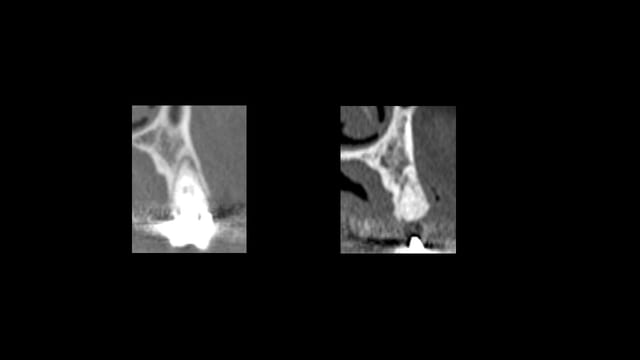

Scanner de contrôle quelques mois plus tard...

Preservation de crete - Eugenol

la procédure a permis de conserver le volume osseux disponible voir même l'augmenter, la difficulté est que le produit de comblement est radio-opaque et que sa cohésion est délicate à aprécier. peut -tu faire part de tes sensations lors du forage.